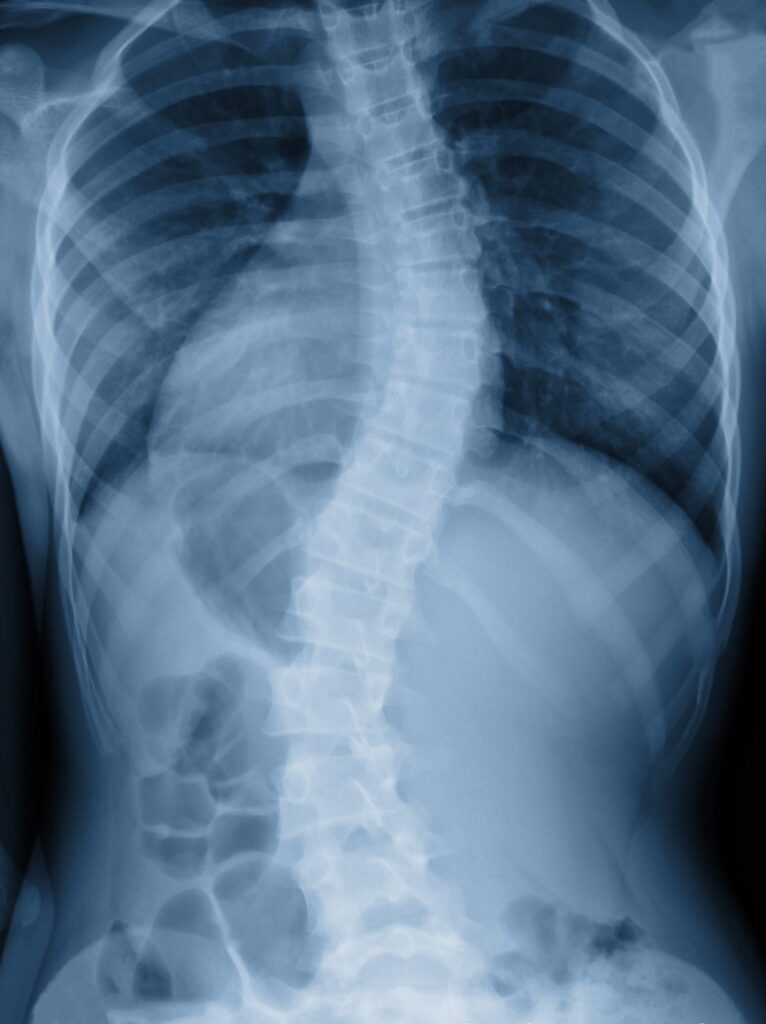

Dotyka około 2-3% osób w wieku rozwojowym i jest trójpłaszczyznową deformacją kręgosłupa, polegającą na jego wykrzywieniu w płaszczyźnie: czołowej, strzałkowej i poprzecznej. Według kryteriów Scoliosis Research Society (SRS) skoliozą nazywamy skrzywienie, w którym kąt odchylenia bocznego kręgosłupa, widoczny w badaniu rentgenowskim, mierzony metodą Cobba (tak zwany kąt Cobba) wynosi co najmniej 10°.

Ze względu na wielkość tego kąta skoliozy obecnie dzielimy na:

- I stopień, skoliozy o kącie 10–24 stopni,

- II stopień, skoliozy o kącie 25–40 stopni,

- III stopień, skoliozy o kącie 50 stopni i powyżej.